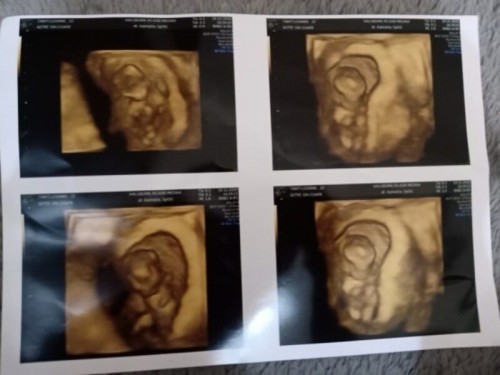

Honey moon after married, yes, di honeymoon ke 2 ini, kami sebagai pasangan yang baru menikah, beneran ganyangka karena ternyata sudah ada anak bayi dikandungan, wow sesuatu berkat yang gapernah kami lupakan, mualnya ketika dijalan, hal yang gabisa dilupain, romantis dan perhatian ayahnya luarbiasa, pulang honeymoon langsung cek dan ternyata usia kandungan sudah 2 minggu😇💑 kami sangat menantikan kehadiran buah hati saat ini #BestMemoriesTAP